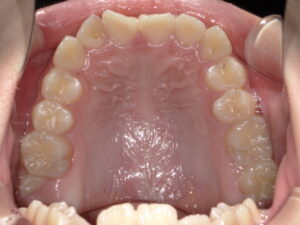

今回の症例の初診時の年齢は12歳1か月で、永久歯への生え変わりがほぼ完了しつつある時期でした。上下顎ともに歯並びのデコボコ・ガタつきが強く、横顔を確認すると出っ歯(上下顎前突)の傾向が認められました。さらに噛み合わせが深く、上下の正中にもずれが見られました。

<初診時>

<上顎>